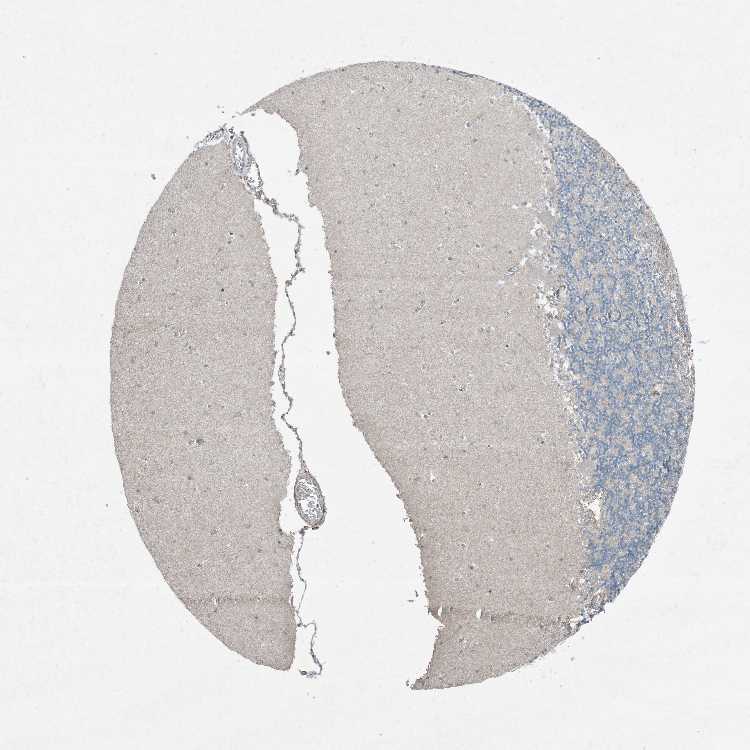

CEREBELLUM - Antibody stainingi

Antibody staining in the annotated cell types in the current human tissue is reported as not detected, low, medium, or high, based on conventional immunohistochemistry profiling in selected tissues. This score is based on the combination of the staining intensity and fraction of stained cells.

Each image is clickable and will lead to virtual microscopy that enables deeper exploration of all samples and also displays staining intensity scores, fraction scores and subcellular localization as well as patient and tissue information for each sample.

Antibody HPA046074Antibody CAB033822

Purkinje cells Not detectedNot detected

Cells in granular layer Not detectedNot detected

Cells in molecular layer Not detectedNot detected